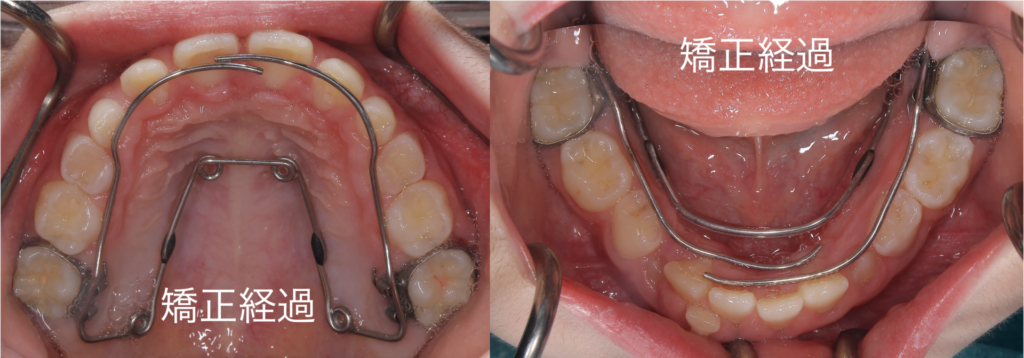

今回は患者様の希望もあり、上顎にはクワドヘリックス、下顎にはバイヘリックスという固定式の装置を用いて治療を行っていきました

治療の経過ですが、アーチが広がり歯が整列してきていることが認められます